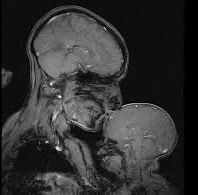

And if you have an extra minute, read the story @rebeccasaxe.bsky.social wrote about making a modern Mother and Child image in an MRI machine. (5/5) www.smithsonianmag.com/science-natu...

MRI image of a parent kissing a baby's forehead.